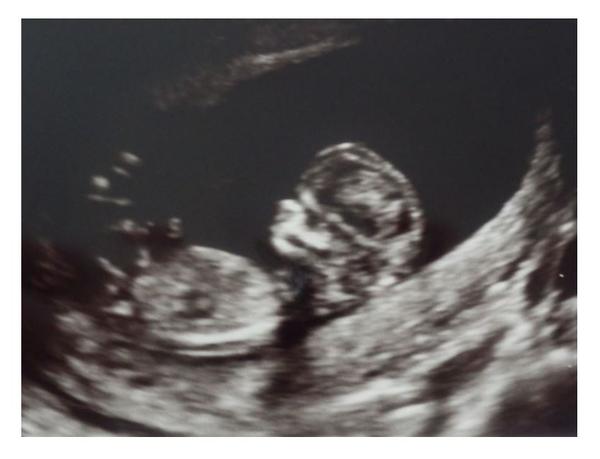

Holčičky, já se s vámi pomalu loučím...i když nakukovat budu asi stále, dokud prďolku nebudu držet v náručí 🙂 Moc vám všem držím pěsti, pokud to nevyšlo napoprvé nebo naponěkolikáté, nezoufejte, vytrvejte, najděte sílu a až budou tělo i mysl skutečně připravené, stopro to vyjde! Holt člověk je tvor složitý a nelze všemu poručit, ale všechno zlé je na něco dobré. Držte se. Jako motivaci pro snažení posílám našeho drobka, jsme po 1.screeningu a vše je zatím naprosto v pořádku ♥

@georgina_ jééééé🙂... to je krásná fotka, než nám odejdeš, chci ti poděkovat za nás všechny🙂... Ve kterým jsi týdnu? Tobě přeji, ať to s prďolkou vydržíte ve zdraví a pohodě až do konce, muck❤

@fonamor O víkendu dokončím 13tt. Děkuju Ti a děkuju za tohle fórum, našla jsem tu odpovědi na spousty otázek, podporu a povzbuzení...dost mi pomohlo, když jsem věděla, že nejsem sama, kdo má problém, a mohla se tu vypsat nebo si přečíst příběhy ostatních 🙂

@georgina_ ty brďo, tak brzo a už je všechno vidět, já čekala, že napíšeš tak pátý měsíc🙂..

@fonamor 😀 ♥ Jj, všechny části a orgány jsou založeny, teď budeme oba jen růst a růst 😀

@romik32 děkujeme 🙂 Neboj, brzy se dočkáš...mně to teda uteklo hrozně rychle, takže ani se nenaděješ a budeš koukat na podobnou fotku 🙂